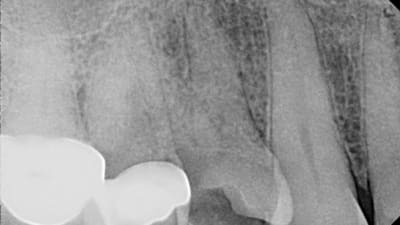

Case Reports Endodontics Case Studies Endodontic Diagnostic Dilemmas: Thorough Examination May Preclude Inappropriate Treatment By Gary Glassman, DDS, Joe Maggio, DDS, Yair Lenga, DDS May 01, 2014 9 min read

Research Update Periodontics Endodontics Histopathologic Changes in Dental Pulp of Teeth with Chronic Periodontitis By Denize Mandarino, MScD, Eliane P. Barboza, DScD, Gilson C. Tristão, DScD, Laila Zarranz, MScD, Telma R. Aguiar, DScD, Vinícius F. Ferreira, MScD May 01, 2014 11 min read